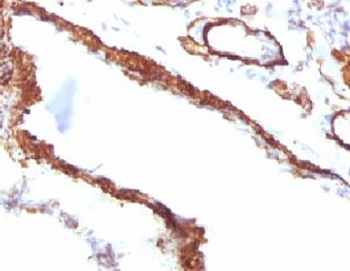

IHC: Formalin-fixed, paraffin-embedded Leiomyosarcoma stained with Smooth Muscle Actin antibody (clone SPM332).